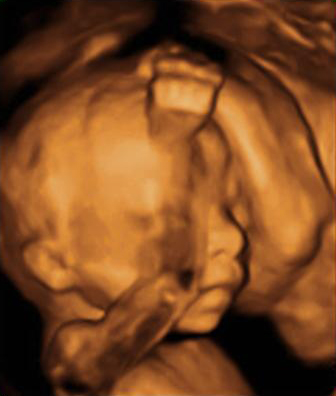

En esta ecografía en 4D se distingue el escroto de este feto varón. En la ecografía de la 20 semanas de embarazo, es muy probable que la embarazada ya sepa el sexo de su bebé, ya que se puede ver en la semana 12. No obstante, ahora se confirma.

Ultrasonido del aparato genital masculino en tres dimensiones

Las imágenes dan buena cuenta del sexo del bebé: se aprecia la pierna, el escroto, el pie y el cordón umbilical de la criatura.